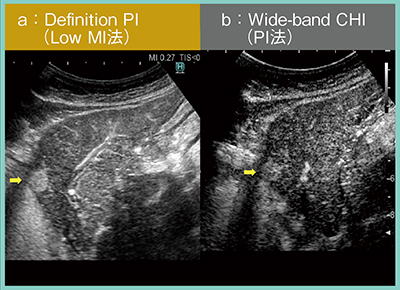

2.血管イメージングを追究した日立のLow MI法“Definition PI”

PI法やAM法のほか,私がよく用いる手法にLow MI法がある。これは,Bモードの音圧(MI値)を下げて造影剤を観察する手法で,現在の高画質化が図られたBモードを背景に造影超音波を実施するため,きわめて高い空間・時間分解能が得られ,特に血管相で有用である。しかし,Bモードを使用するため,造影モードから切り替える手間や,造影モード特有の機能が使用できないというワークフローの問題があるほか,性能面ではSNRが悪化し,造影感度も低下する。

そこで,日立は今回,造影モードの1つとしてLow MI法を組み込み,さらに,機能や条件を工夫することで,造影検査時にストレスなく簡便に使用できる新しい血管イメージングDefinition PIを構築した。これにより,造影モードのままLow MI法が使用可能となったほか,内部パラメータの改善によりSNRが改善し,MI値の最適化によって造影感度が向上した。また,造影モードにおいてもコンパウンドに対応したことで,血管走行の描出力の向上が図られた。

症例1の動脈相について,従来のPI法とDefinition PIを比較したところ,Definition PIでは感度および血管走行の描出能が飛躍的に向上し,腫瘍が濃染する様子が明瞭であった(図4)。

図4 症例1:動脈相におけるDefinition PIとPI法の比較